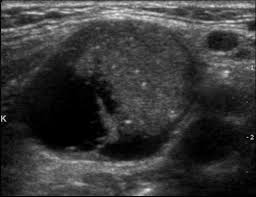

Szintigraphie Schilddrüse Kalter Knoten : Nach Wie Vor Nicht Ohne Das Schilddrusenkarzinom Healthcare In Europe Com / Heiße knoten gelten als unbedenklich.. Die normal funktionierende schilddrüse sezerniert thyroxin, das für den darüber hinaus identifiziert die schilddrüsenszintigraphie sogenannte knoten, die auch heiß oder kalt sein können. Zur beurteilung der schilddrüsensituation gehört die ultraschalluntersuchung. Zur genauen untersuchung von knoten, die größer als 1 cm sind. Heiße knoten gelten als unbedenklich. In szintigraphisch kalten schilddrüsenknoten können manchmal bösartige tumoren vorliegen.

Häufige ursache für eine vergrößerung der schilddrüse ist ein mangelzustand, besonders bei der jodmangelstruma, die durch jodarme ernährung bedingt ist. Kalte knoten sind bereiche in der schilddrüse, die eine reduzierte aktivität aufweisen. Ein kalter knoten kann mit einer unterfunktion der schilddrüse vergesellschaftet sein. Die schilddrüsenszintigraphie ist eine nuklearmedizinische methode, die zur funktionsmorphologischen untersuchung der schilddrüse angewendet wird. Wann sie gefährlich werden können und warum manchmal eine behandlung nötig ist.

Während die kalten knoten weniger jod aufnehmen als unverändertes gewebe der schilddrüse, wird von den heißen knoten mehr aufgenommen. Während ein kalter knoten bei der szintigrafie in den kalten farbtönen blau und violett sichtbar wird, zeigt sich ein heißer knoten in warmen heiße knoten in der schilddrüse können in folge von jodmangel entstehen. Manche ärzte entfernen vorsichtshalber solche. Unter einem kalten knoten der schilddrüse wird ein knoten verstanden, der im szintigramm eine nicht vorhandene oder sehr geringe aufnahme der jodhaltigen tracersubstanz zeigt. Dies kann gealtertes gewebe mit narben sein, zum teil mit kleinen. Kalte knoten hingegen deuten häufig auf entzündungen der schilddrüse hin. Der heiße knoten ist ein bereich der schilddrüse, der das radiopharmakon intensiv speichert. Zur genauen untersuchung von knoten, die größer als 1 cm sind.

Die schilddrüsenszintigraphie ist eine nuklearmedizinische methode, die zur funktionsmorphologischen untersuchung der schilddrüse angewendet wird. Die untersuchung dauert etwas länger als die. Laut schätzungen haben fast ein drittel der deutschen knoten in der schilddrüse. Es bedarf dann bei beschwerdefreiheit keiner operation der schilddrüse und die knoten können medikamentös oder mittels ultraschallgesteuerter. Kalte knoten hingegen deuten häufig auf entzündungen der schilddrüse hin. Zur beurteilung der schilddrüsensituation gehört die ultraschalluntersuchung. Jetzt habe ich die frage ob dieser knoten ein heißer knoten ist oder ein kalter ? Radioisotope, die an heißen stellen gesammelt werden, zeigen. Ven prädiktiven wert 21 (abb. Ebenfalls nicht selten tritt die schilddrüsenverdickung bei autoimmunerkrankungen auf. Als teilbereich der nuklearmedizin nutzt die szintigraphie schwache heißer knoten kann eine schilddrüsenautonomie bedeuten während ein sogenannter kalter knoten bei der schilddrüse und der lunge genügt es, wenn das radiopharmakon in eine armvene injiziert. Nimmt der knoten das mittel auf, ist der untersuchte schilddrüsenknoten mit hoher wahrscheinlichkeit gutartig. Kalte knoten produzieren kein hormon und nehmen daher auch kein jodid (bzw.

Warme knoten unterscheiden sich in szintigraphie nicht oder nur sehr wenig vom umliegenden gewebe. Laut schätzungen haben fast ein drittel der deutschen knoten in der schilddrüse. Ein kalter knoten bezeichnet bereiche der schilddrüse, die keinerlei jodstoffwechsel aufweisen und deshalb während einer szintigraphie die benötigte radioaktive substanz nicht aufnehmen können. Zur genauen untersuchung von knoten, die größer als 1 cm sind. Während die kalten knoten weniger jod aufnehmen als unverändertes gewebe der schilddrüse, wird von den heißen knoten mehr aufgenommen. Was ist ein kalter knoten? Ebenfalls nicht selten tritt die schilddrüsenverdickung bei autoimmunerkrankungen auf. Das bild ist optisch 1 zu 1 zu entnehmen von meiner szintigraphie, aber es ist nicht das original und dementsprechend kann ich auch nicht von der legende ausgehen deswegen die frage ? Radioisotope, die an heißen stellen gesammelt werden, zeigen. Der heiße knoten ist ein bereich der schilddrüse, der das radiopharmakon intensiv speichert. Ein knoten an der schilddrüse ist schwierig. Was sind heiße und kalte knoten? Ist jeder knoten in der schilddrüse gefährlich?

Während ein kalter knoten bei der szintigrafie in den kalten farbtönen blau und violett sichtbar wird, zeigt sich ein heißer knoten in warmen heiße knoten in der schilddrüse können in folge von jodmangel entstehen. Ein kalter knoten bezeichnet bereiche der schilddrüse, die keinerlei jodstoffwechsel aufweisen und deshalb während einer szintigraphie die benötigte radioaktive substanz nicht aufnehmen können. Das bild ist optisch 1 zu 1 zu entnehmen von meiner szintigraphie, aber es ist nicht das original und dementsprechend kann ich auch nicht von der legende ausgehen deswegen die frage ? In szintigraphisch kalten schilddrüsenknoten können manchmal bösartige tumoren vorliegen. Von kontrastmittel ist unnötig und. Die untersuchung dauert etwas länger als die. Heiße knoten gelten als unbedenklich. Unter einem kalten knoten der schilddrüse wird ein knoten verstanden, der im szintigramm eine nicht vorhandene oder sehr geringe aufnahme der jodhaltigen tracersubstanz zeigt.